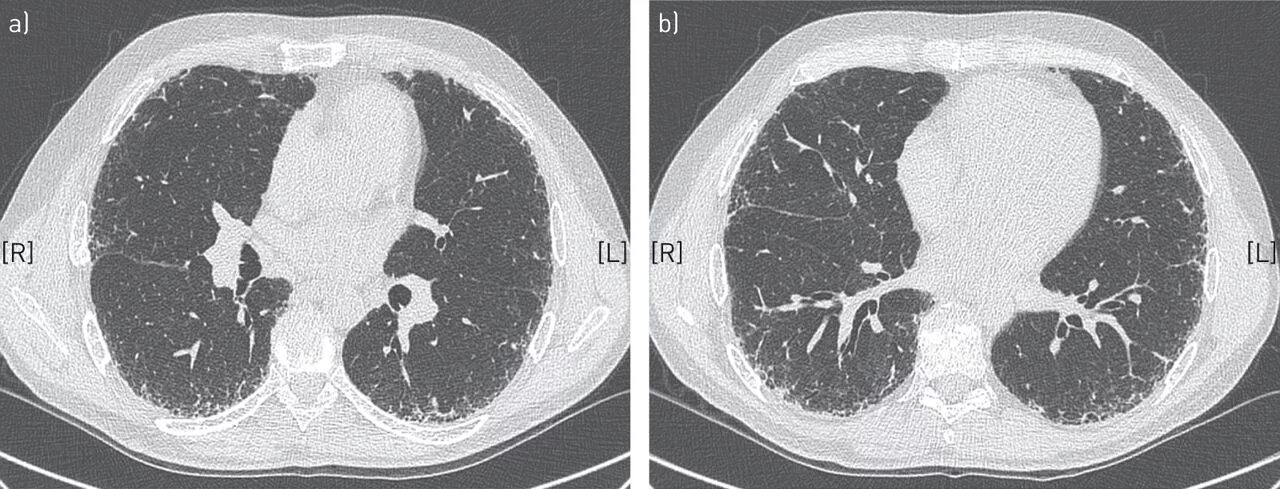

Фиброз кт